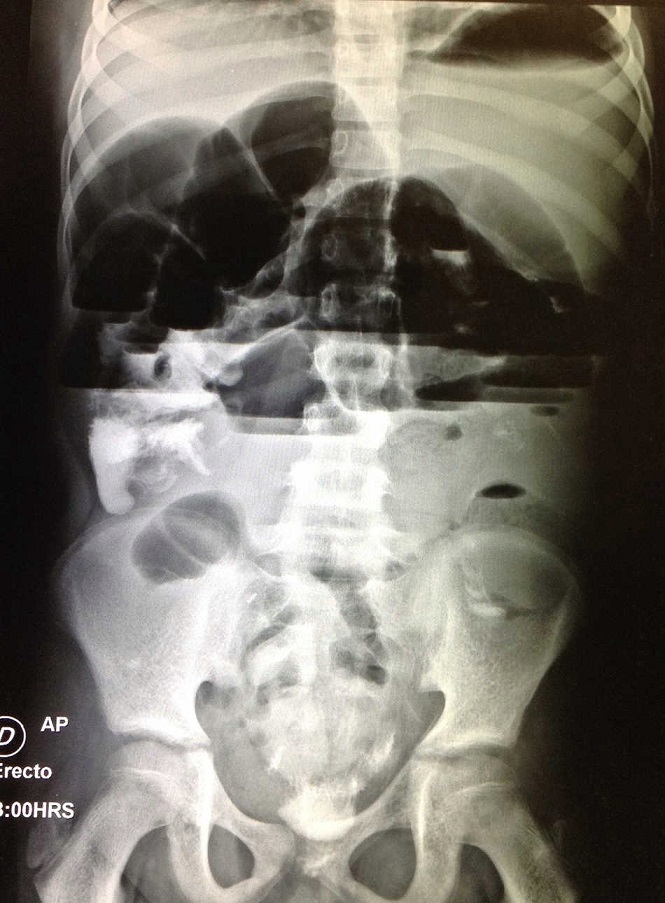

Paciente masculino de 13 años de edad, sin antecedentes heredofamiliares de importancia, con antecedentes perinatales de embarazo gemelar que se obtiene por cesárea y requiere maniobras avanzadas de reanimación. Presentó desarrollo psicomotor alterado consecuente a asfixia perinatal, por lo que desde los 2 años de edad acude a terapia de neurodesarrollo. A los 11 años de edad fue diagnosticado con insuficiencia renal crónica por hipoplasia renal bilateral, y se trató mediante diálisis peritoneal hasta los 12 años. Se realizó trasplante renal, colocándose en la fosa iliaca derecha, conservando ambos riñones hipoplásicos, con régimen de tratamiento inmunosupresor incluyendo: tacrolimus, prednisona, azatioprina y micofenolato sódico, y medicamentos de forma crónica: ketoconazol, hierro, trimetoprim/sulfametoxazol. Inició su padecimiento actual 3 semanas previas a su ingreso al presentar dolor abdominal leve, intermitente, de tipo urente, localizado en epigastrio con irradiación a mesogastrio, sin fenómenos desencadenantes o atenuantes, acompañado de tres a cuatro evacuaciones por día, disminuidas en consistencia, semilíquidas, de coloración verdosa, sin moco ni sangre, no fétidas. El dolor se volvió progresivo, hasta que 24 horas previas a su ingreso se tornó de intensidad moderada, presentando aumento de intensidad hasta ser incapacitante, por lo que acudió a la unidad de urgencias. A la exploración física el abdomen se encontró globoso, con cicatriz en flanco derecho, depresible, con dolor a la palpación profunda en epigastrio y mesogastrio. Sin datos de abdomen agudo, timpánico a la percusión, peristalsis presente en los cuatro cuadrantes. Se ingresó al hospital agregándose pantoprazol a su tratamiento crónico de base, y se suspendió el trimetoprim/sulfametoxazol, la ferranina y el micofenolato sódico. Los resultados de la biometría hemática completa revelaron anemia con hemoglobina 10.8 g/dl, leucopenia de 1.6/ul y neutropenia 0.54/ul, consecuente a la insuficiencia renal crónica e inmunosupresores. El examen general de orina no presentó alteraciones. Los resultados del perfil bioquímico fueron: creatinina: 0.9 mg/dl (tasa de filtración glomerular estimada: 107.3 ml/min/1.73 m2, lo cual se encuentra en rangos normales), nitrógeno de la urea: 20 mg/dl, urea: 42.8 mg/dl, calcio total: 8.9 mg/dl, fósforo 3.3 mg/dl, albúmina 3.4 g/dl, TGO (AST): 11 U/l, TGP (ALT): 8 U/l, fosfatasa alcalina: 98U/l, deshidrogenasa láctica: 297U/l, sodio: 132.2 meq/l, potasio: 3.63 meq/l, cloro: 100.9 meq/l. Los niveles de tacrolimus fueron de 5.6 ng/ml (5ng/ml dosis normal de transplante de riñón de >6 meses). Se realizó una tomografía contrastada de abdomen, donde únicamente se observaron asas de intestino delgado dilatadas e injerto renal en buen estado. Se realizó un tránsito gastrointestinal, el cual no reportó datos de obstrucción. Durante los primeros días de estancia hospitalaria se manejó el dolor con butilhioscina; sin embargo, progresivamente aumentó la distensión abdominal, por lo que se realizó una radiografía simple de abdomen, en donde se muestran niveles hidroaéreos y distensión intestinal (Fig. 1). Se realizó interconsulta con el servicio de cirugía de adultos, ya que fue el mismo equipo que participó en el trasplante del paciente, y ellos colocaron una sonda nasogástrica, la cual drena material fecaloide. El paciente se mantuvo en observación con radiografías de control; sin embargo, continuó con dolor y distensión abdominal progresiva de hasta 78 cm de perímetro abdominal, por lo que se realizó laparotomía exploratoria (LAPE). Este estudio reveló la presencia de adherencias con predominio a nivel de yeyuno e íleon y un divertículo de Meckel que se resecó y se realizó anastomosis. Posterior a la cirugía, el paciente presentó inestabilidad hemodinámica y fue transferido a la unidad de cuidados intensivos pediátricos.

Figura 1 Radiografía simple de abdomen de pie: Importante distensión de asas de intestino delgado además de niveles hidroaéreos.